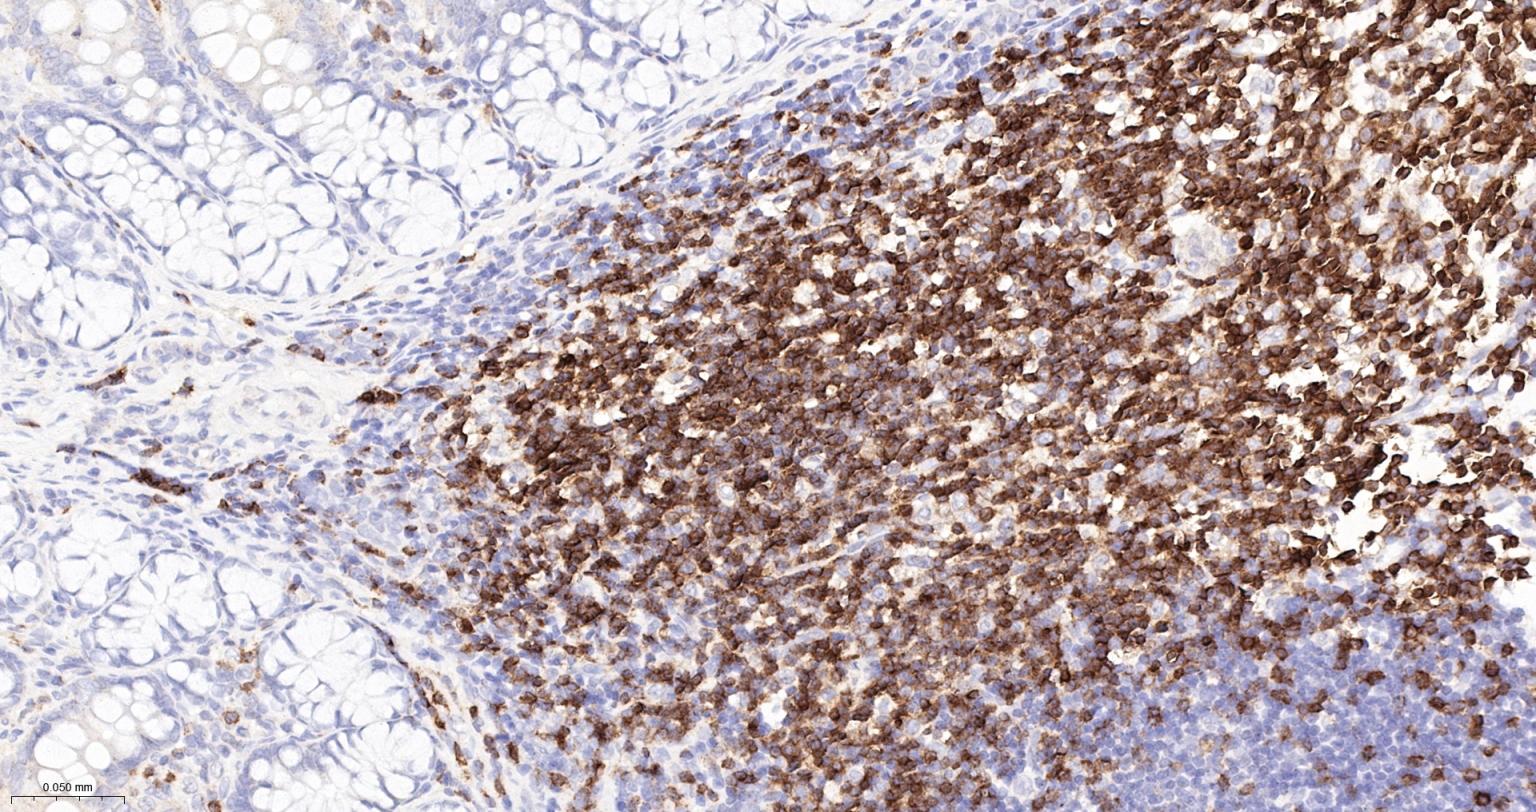

Paraformaldehyde-fixed, paraffin embedded Human Tonsil; Antigen retrieval by boiling in sodium citrate buffer (pH6.0) for 15 min; The section was incubated with CD3E Monoclonal Antibody, Unconjugated (bsm-60002R) at 1:500 overnight at 4°C, followed by conjugation to the bs-0295G-HRP and DAB (C-0010) staining.